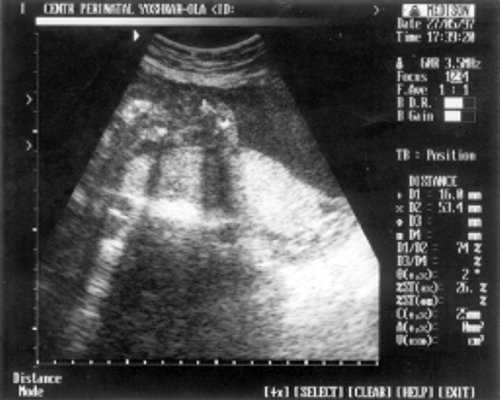

- ДБ (длина бедра) = 24 мм - 17 нед. (рис. 2)

Рис. 2. УЗИ плода - бедро.